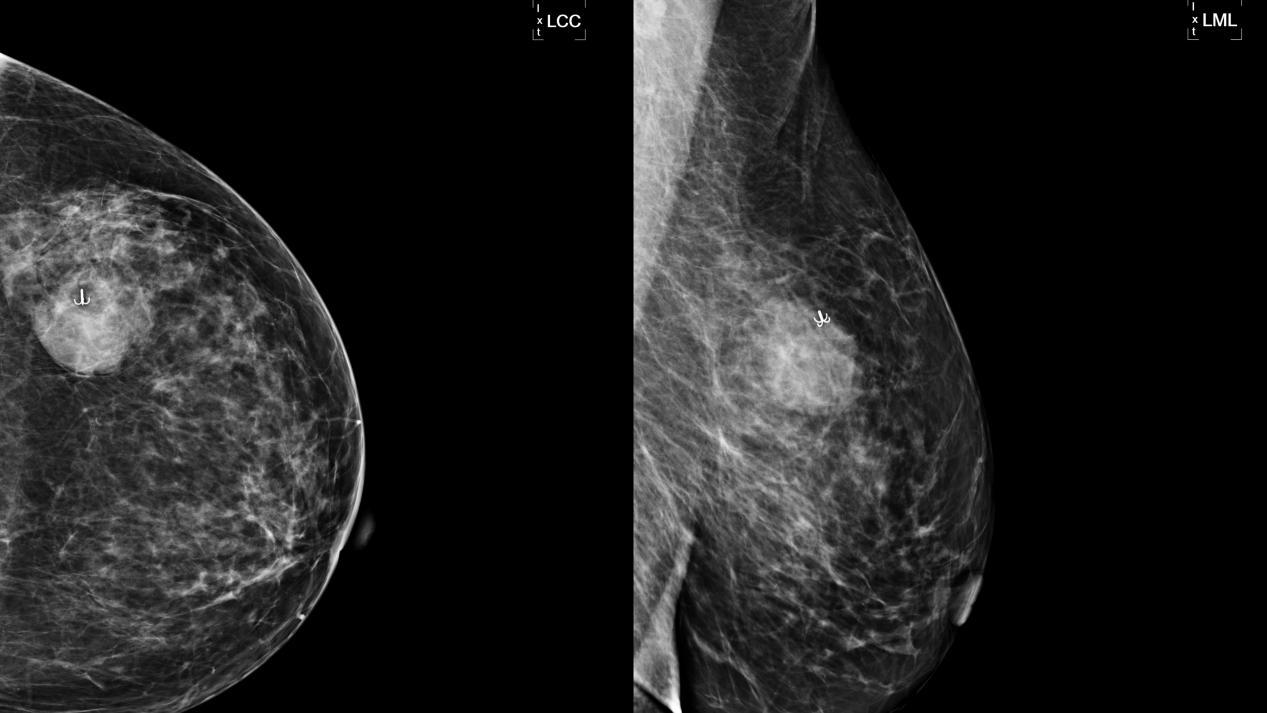

术前,我院甲乳外科二病区林明副主任医师和北区放射科刘璇婷主治医师共同查阅了赵女士的钼靶影像资料,术中,根据钼靶定位结果,完整切除了肿块,手术获得成功,目前患者已经康复出院。此例钼靶引导下定位技术属皖东地区首例,填补了皖东地区该项技术空白。

▲定位针定位乳房肿块